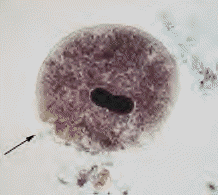

• "Balantidium coli trophozoites.  These are characterized by:

• their large size (40 µm to more than 70 µm)

• the presence of cilia on the cell surface - particularly visible in (B)

• a cytostome (arrows)

• a bean shaped macronucleus which is often visible - see (A), and a smaller, less conspicuous micronucleus"

• courtesy of the Division of Parasitic Diseases at the National Center for Infectious Diseases, Centers for Disease Control & Prevention